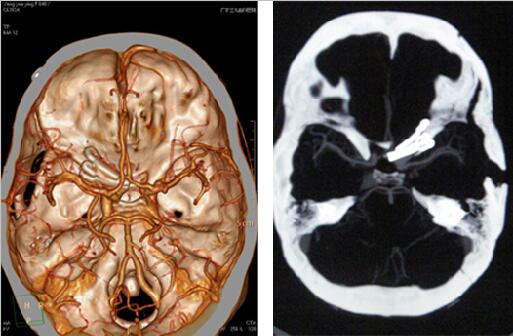

经过术前严格的方案制定及规范的Matas训练后,于8月1日为患者实施手术。术前先置入球囊,并行球囊阻塞耐受试验,术中暴露动脉瘤后充盈球囊闭塞颈内动脉近端,最后夹闭动脉瘤。手术过程非常顺利,术后患者所有生命体征都平稳。经过3周的休养,杨女士康复出院。该手术的成功,标志着我院动脉瘤手术水平已达到国内先进行列。

术后检查结果